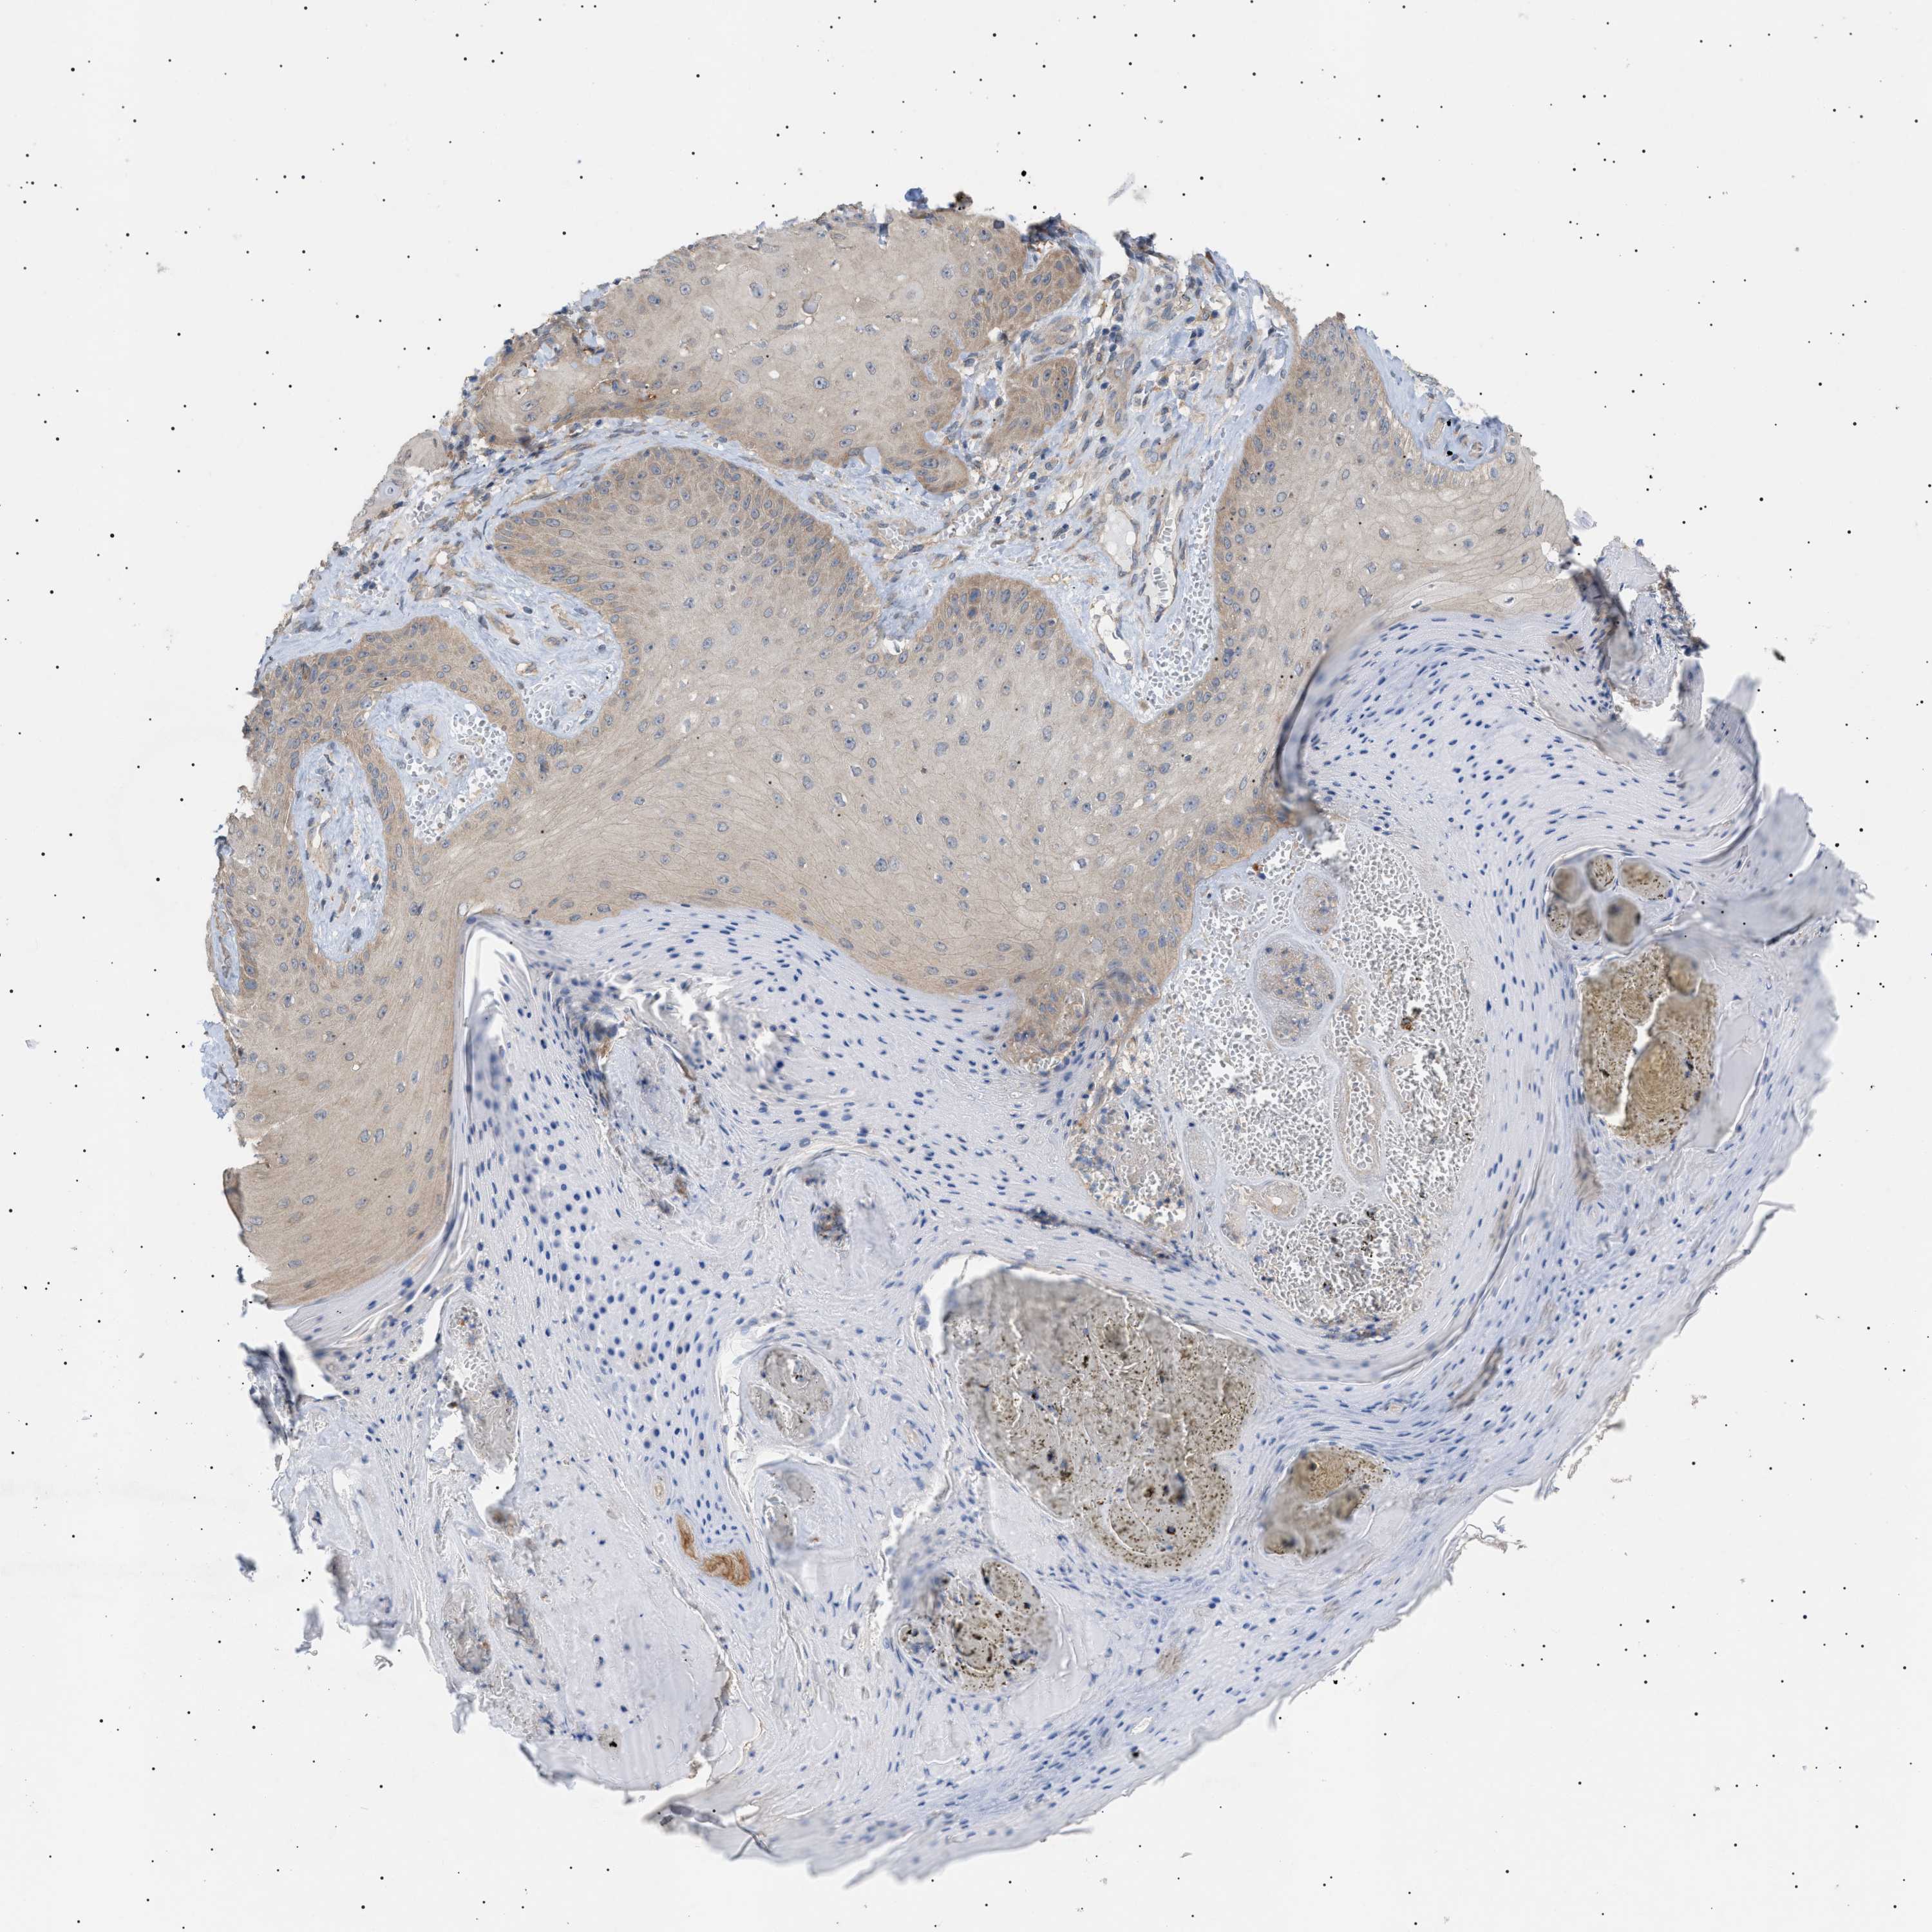

CANCER SKIN CANCER Show tissue menu

SKIN CANCER - Protein expressioni

A mouse-over function shows sample information and annotation data. Click on an image to view it in a full screen mode. Samples can be filtered based on level of antibody staining by selecting one or several of the following categories: high, medium, low and not detected. The assay and annotation is described here.

Each image is clickable and will lead to virtual microscopy that enables deeper exploration of all samples and also displays staining intensity scores, fraction scores and subcellular localization as well as patient and tissue information for each sample.

Antibody CAB016944

Staining

High

Medium

Low

Not detected

Intensity

Strong

Moderate

Weak

Negative

Quantity

>75%

75%-25%

<25%

None

Location

Nuclear

Cytoplasmic/membranous

Cytoplasmic/membranous,nuclear

Basal cell carcinoma